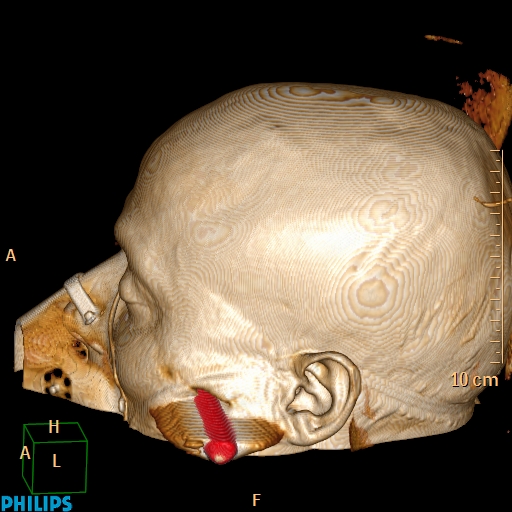

Accident de travail, chute sur une barre de fer. La barre de fer a été coupé sur le chantier pour dégager le patient A noter, comme on peut le voir sur la dernière image, que le patient était conscient et réveillé